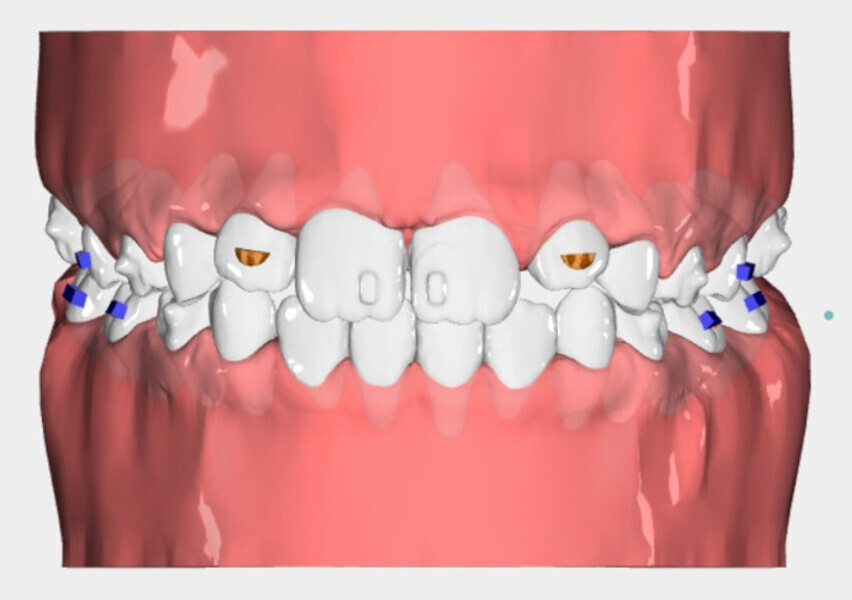

The 8-year-old male patient presented with a diastema between teeth #11 and 21 and non-eruption of teeth #12 and 22 (Fig. 1). The patient underwent a thorough orthodontic examination, including intra-oral photographs, extra-oral photographs, cephalometric radiography of the skull with cephalometric tracing, dental panoramic tomograms, impressions by intra-oral scanning, and functional and phonetic tests. Intra-oral examination (Fig. 2) and pattern analysis showed a Class I molar and canine relationship and contraction of the maxillary arch, displaced pre-contact between teeth #63 and 73, a 3.7 mm diastema between teeth #11 and 21, a mandibular midline deviation to the left, a maxillary midline to the right, and an open bite (−1.5 mm).

After 18 months of therapy, a case reassessment was carried out to verify that the goals had all been achieved (Fig. 8). Comparison of extra-oral photographs at the start of treatment (T0) and end of treatment (T1; Fig. 9) showed that excellent balance of the patient’s face had been achieved with a regular, symmetrical smile. Comparison of the intra-oral photographs (Fig. 10) and models (Fig. 11) also showed wider and more harmonious arch forms, closure of the anterior diastema, closure of the open bite and recentring of the mandibular midline. Excellent gingival trophism had also appeared.